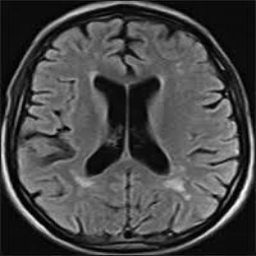

• Brain Tumor MRI Dataset (BMRI) [33]: The three datasets below are combined to create this dataset: figshare, SARTAJ, Br35H. There are 7023 MRI images of the human brain in this collection, divided into 4 categories: pituitary, glioma, meningioma, and no tumor. Images categorized as the ’no tumor’ class were obtained from the Br35H dataset.

The proposed QMedShield’s security is evaluated using a number of metrics and proved that it is resistant to various cryptographic attacks including brute-force attacks, statistical attacks, histogram attacks, and differential attacks. Throughout the section, 6 sample medical images BMRI1,BMRI2,CXR1,CXR2,LCT1,LCT2𝐵𝑀𝑅subscript𝐼1𝐵𝑀𝑅subscript𝐼2𝐶𝑋subscript𝑅1𝐶𝑋subscript𝑅2𝐿𝐶subscript𝑇1𝐿𝐶subscript𝑇2BMRI_{1},BMRI_{2},CXR_{1},CXR_{2},LCT_{1},LCT_{2} are taken (2 images from each dataset) to show the performance comparison. The selection of MRI, X-ray, and CT images for the encryption task aims to demonstrate the versatility and effectiveness of our model across various imaging modalities, showcasing its applicability and robustness in diverse clinical scenarios. Figure 11 shows the selected sample medical images and their corresponding encrypted images.

Refer to caption

(a) BMRI1𝐵𝑀𝑅subscript𝐼1BMRI_{1}

(b) CXR1𝐶𝑋subscript𝑅1CXR_{1}

(c) LCT1𝐿𝐶subscript𝑇1LCT_{1}

(d) BMRI2𝐵𝑀𝑅subscript𝐼2BMRI_{2}

(e) CXR2𝐶𝑋subscript𝑅2CXR_{2}

(f) LCT2𝐿𝐶subscript𝑇2LCT_{2}

(g) E(BMRI1)𝐸𝐵𝑀𝑅subscript𝐼1E(BMRI_{1})

(h) E(CXR1)𝐸𝐶𝑋subscript𝑅1E(CXR_{1})

(i) E(LCT1)𝐸𝐿𝐶subscript𝑇1E(LCT_{1})

(j) E(BMRI2)𝐸𝐵𝑀𝑅subscript𝐼2E(BMRI_{2})

(k) E(CXR2)𝐸𝐶𝑋subscript𝑅2E(CXR_{2})

(l) E(LCT2)𝐸𝐿𝐶subscript𝑇2E(LCT_{2})

Figure 11: Selected sample plain medical images and the corresponding encrypted cipher images